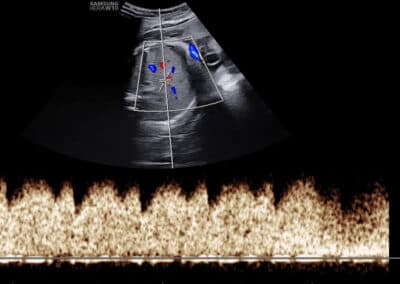

Dopplerovské vyšetření ductus venosus – normální nález (pozitivní a-vlna s PI do 1.3)

Dopplerovské vyšetření ductus venosus – abnormální nález (reverzní a-vlna s PI nad 1.3)

UZ vyšetření průtoku v ductus venosus dle FMF protokolu

Protokol pro správné Dopplerovské vyšetření průtoku krve v ductus venosus:

CRL 45-84 mm (11-13+6 týden) Vyšetření musí být provedeno během klidové fáze (absence pohybů) plodu Zvětšení (hrudník a břicho plodu vyplňují většinu obrazovky) Mid-sagitální řez tělem plodu, barevné Dopplerovské zobrazení toku krve v pupečníkové žíle, ductus venosus a v srdci Gate 0.5-1mm přes ductus venosus (místo aliasingu – světlé barvy při Dopplerovském vyšetření) Odklon průběhu v ductus venosus 0-30º od vertikální osy Nízký filtr (50-70 Hz) Vysoká rychlost posunu křivky (2-3cm/s)